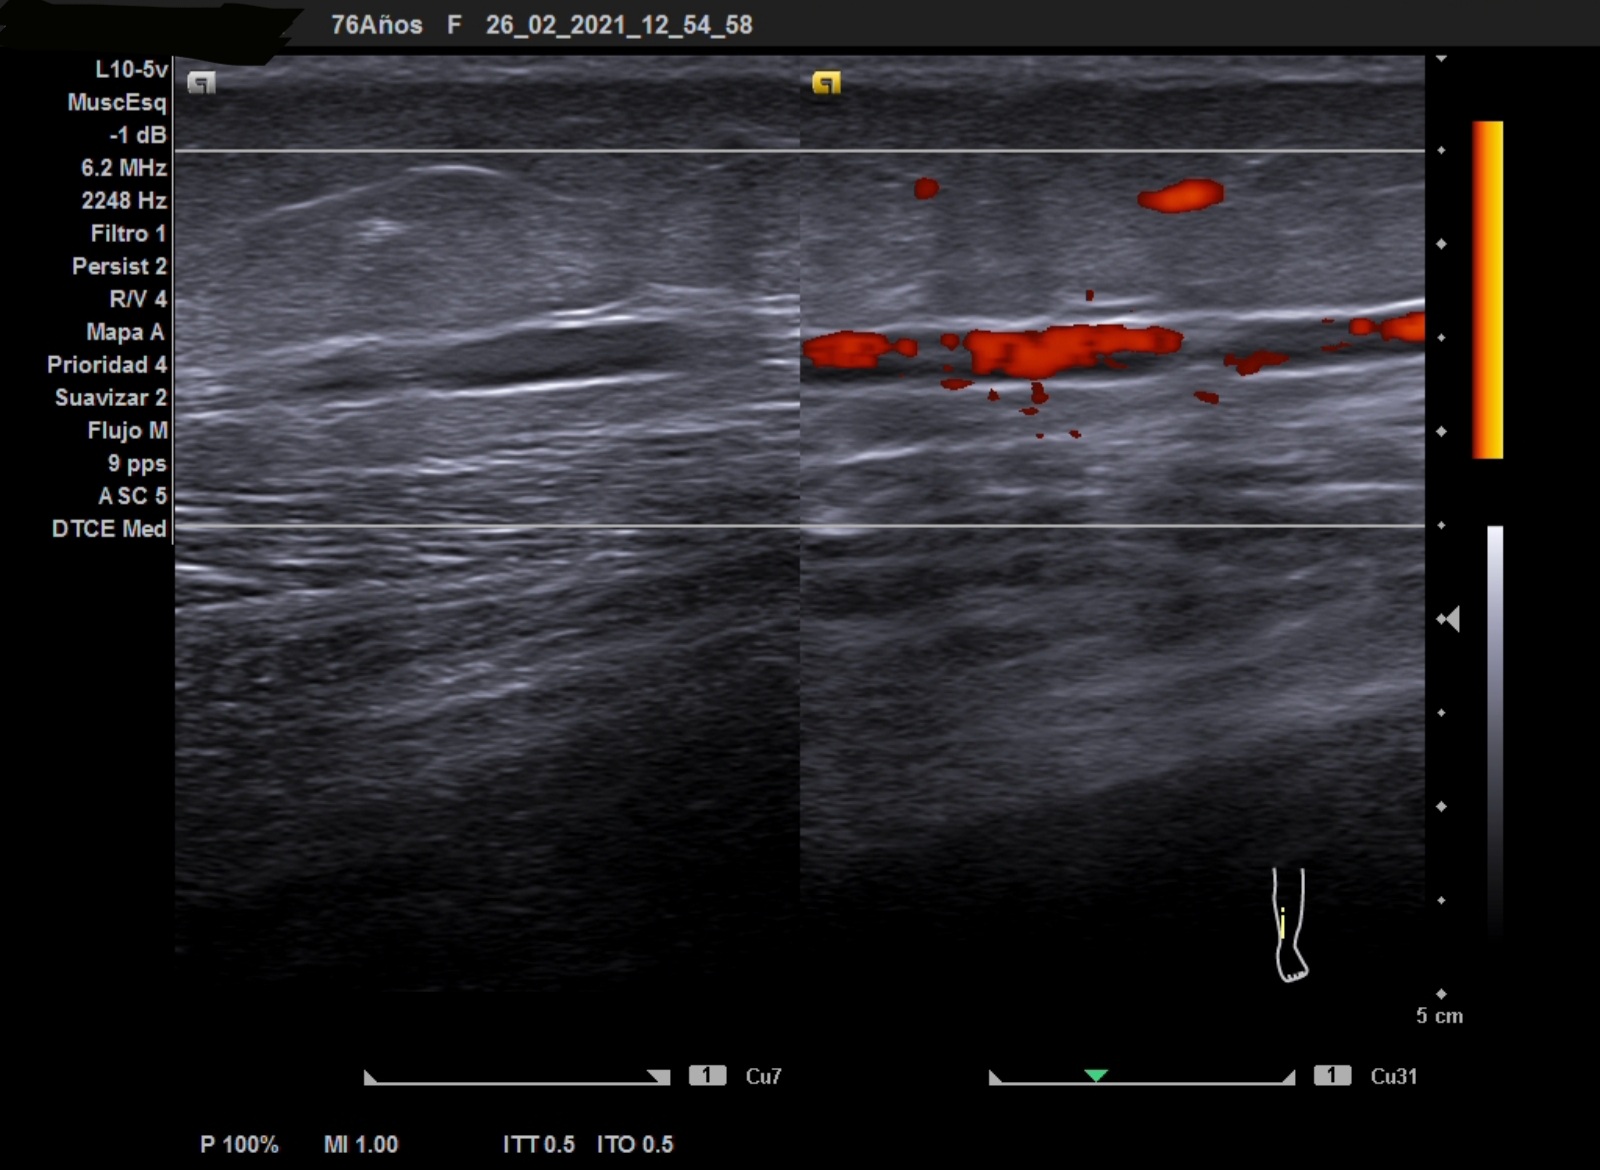

Ecografía clínica: no compresibilidad venosa, con signo de «oleada» negativo en venas tibiales posteriores.

Debemos conocer los signos ecográficos de la trombosis venosa: ausencia de flujo venoso, no compresibilidad, «oleada» negativo, material ecogénico intraluminal según la fase en la que esté y sin captación Doppler pulsado. En caso de tromboflebitis la localización será superficial. La rotura de fibras con clínica de dolor súbito como «una pedrada». La rotura de un quiste de Baker en cara posterior de la rodilla.